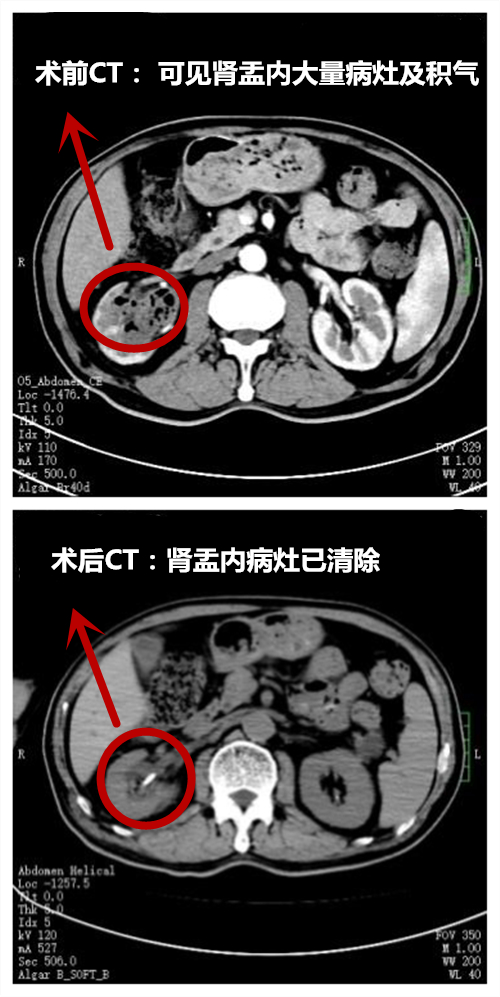

经积极控制感染,密切监测血糖等术前准备和讨论后,以刘哲主任医师为主的手术团队为陈先生实施了全麻下右侧经皮肾镜下负压鞘吸引结合钬激光击散脓苔+膀胱脓肿清除+输尿管双J管内引流。手术只需在患者肾脏部位穿刺筷子尖大小的小孔,利用负压吸引技术,快速清除肾盂及膀胱内脓性分泌物,术中出血量仅5mL。术后,护理团队为患者实施个性化加速康复护理,术后1周,复查CT病灶清除干净。目前,患者排尿顺畅,小便清亮,已康复出院。